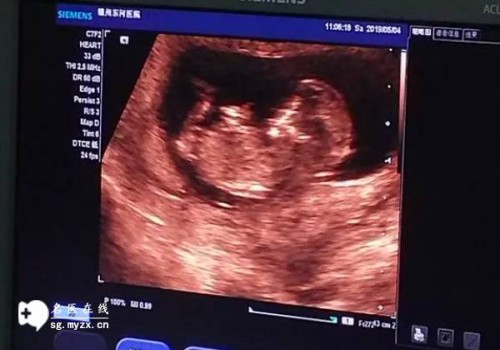

囊胚的移植主要可以提高做试管婴儿的成功率,并且也能降低宫外孕的发生,但移植囊胚并不能预防胎儿的畸形。0pn囊胚可能不是质量好的囊胚,但移植后只要没有异常,那么也是能成功怀上孩子的,虽然做试管婴儿也存在这怀孕后胎儿畸形的可能,但概率上是比较低的,具体如下:

不成功,0pn胚胎不适合移植,对于很多0pn胚胎养囊移植的女性面临的风险其实也是比较大的,如果移植了0pn囊胚最好是定期进行产前检查,一旦有任何不适,最好及时就医。